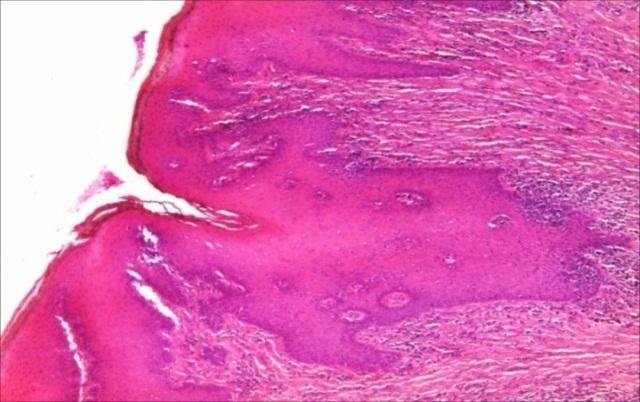

Pseudoepitheliomatous hyperplasia, also called Heck's disease, is an epithelial, inconstant and conjunctive proliferation that develops as a response to a great variety of stimuli. It is a lesion associated to different diseases, being found in the following etiopathogenic conditions: infectious pathogenic conditions, tumoral pathogenic conditions, inflammatory pathogenic conditions. We studied oral pseudoepitheliomatous hyperplasia for which we performed a histopathological study, on a group of 47 cases of oral pseudoepitheliomatous hyperplasias, where we investigated the following: oral epithelium changes, changes in the underlying lamina propria and associated etiopathogenic conditions. The main changes of the oral epithelium were: elongation of the epithelial apexes (17.02%), acanthosis (100%), dyskeratosis (14.89%), and in the underlying lamina propria: fibrosis (29.78%), inflammatory infiltrate (70.21% and vascular proliferation (10.64%). The most frequent associated etiopathogenic conditions were the infectious ones (55.31%), followed by the tumoral ones (29.79%), on the last place being the inflammatory conditions (14.89%).

假上皮瘤样增生,也称为赫克病,是一种上皮性、非恒定的结缔组织增生,是对多种刺激的反应。它是一种与不同疾病相关的病变,见于以下病因情况:感染性致病情况、肿瘤性致病情况、炎症性致病情况。我们对一组47例口腔假上皮瘤样增生进行了组织病理学研究,以研究口腔假上皮瘤样增生,我们调查了以下方面:口腔上皮变化、其下方固有层的变化以及相关的病因情况。口腔上皮的主要变化为:上皮顶端伸长(17.02%)、棘层增厚(100%)、角化不良(14.89%),在下方固有层的变化为:纤维化(29.78%)、炎症浸润(70.21%)和血管增生(10.64%)。最常见的相关病因情况是感染性病因(55.31%),其次是肿瘤性病因(29.79%),排在最后的是炎症性情况(14.89%)。